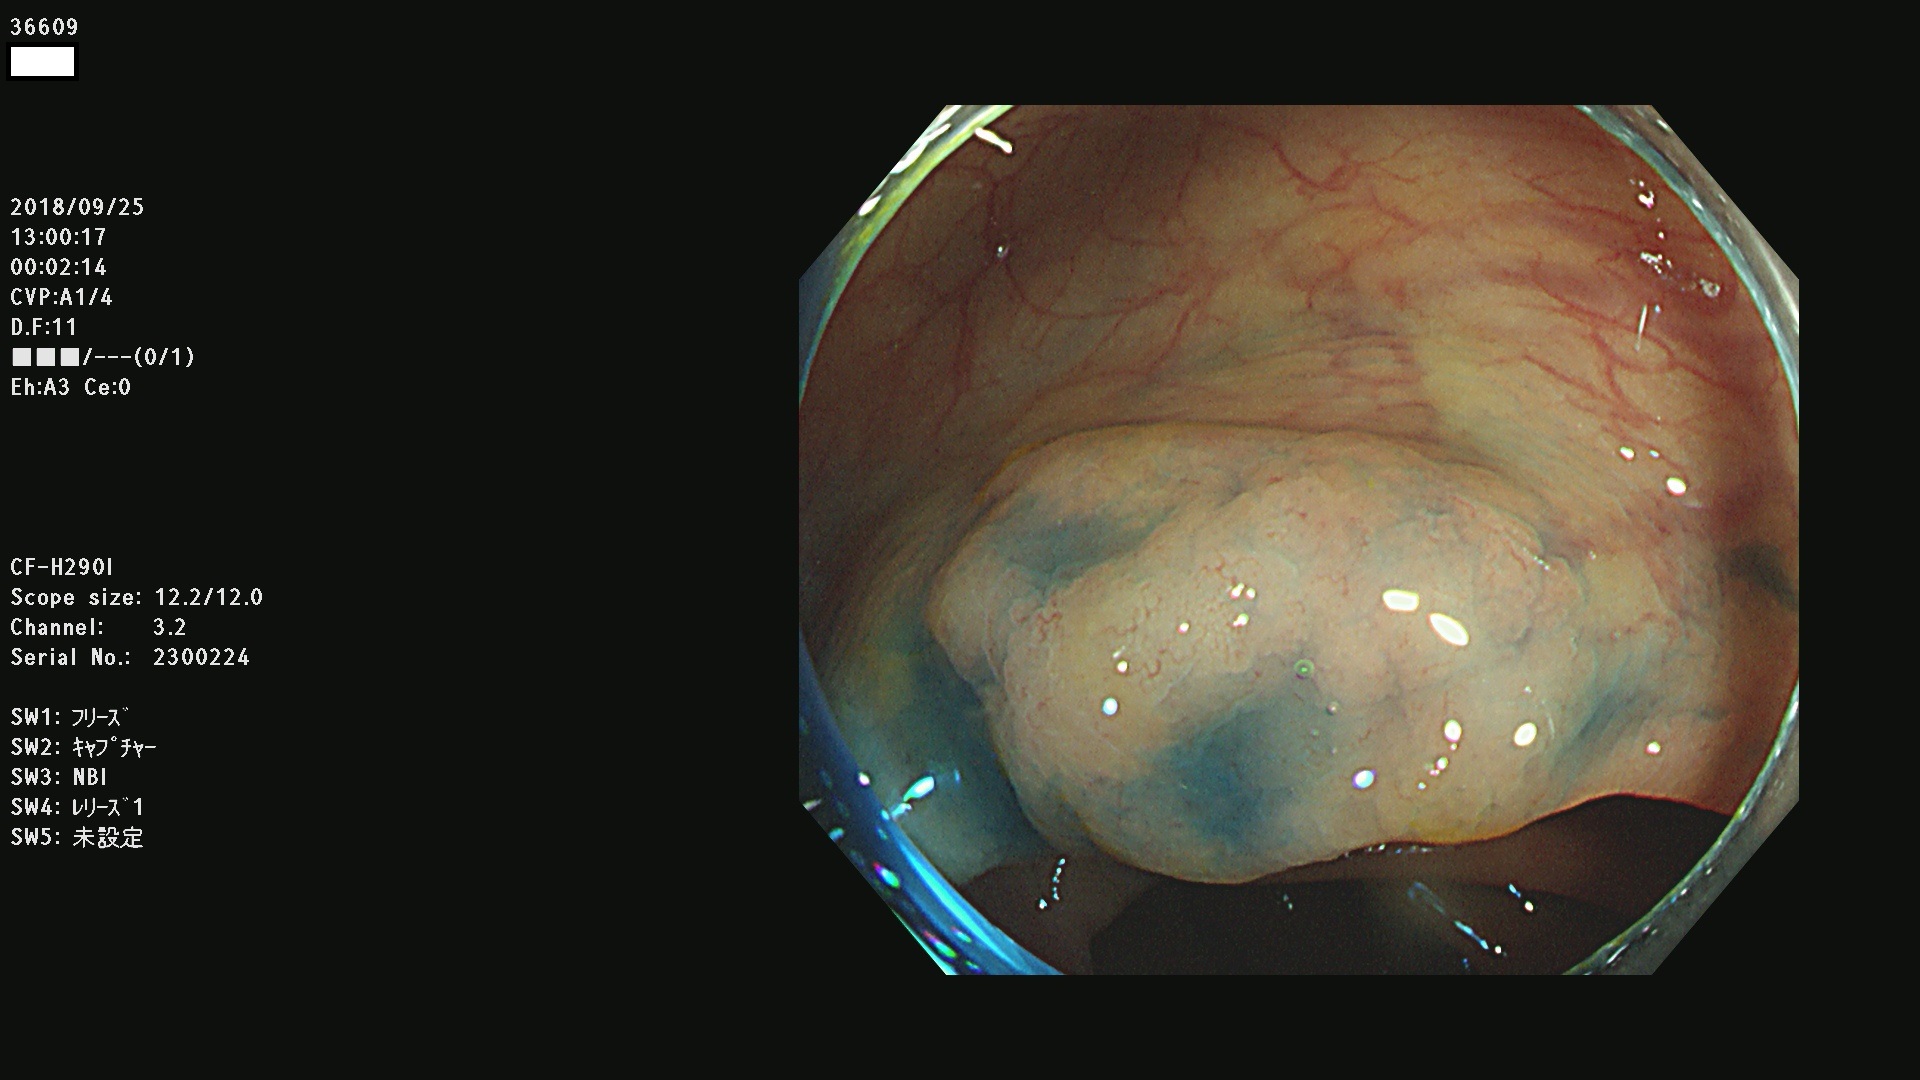

36600 36601 36603 36605 36606 36608 36609 36610 36611 36612 36613 36615 36617 36620 36621 36624 36625 36626 36627 36628 36629 36631(SSAPのみ) 36632 36633 36634 36636(SSAPのみ) 36637(SSAPのみ) 36639 36640 36642 36643 36644 36646 36647 36648 36649(SSAPのみ) 36650(SSAPのみ) 36652 36653 36654 36655(SSAPのみ) 36656 36657 36658 36659 36660 36661(SSAPのみ) 36665 36668 36669 36672 36673 36676 36677 36678 36679 36681 36682 36683 36684 36685 36687(SSAPのみ) 36691 36692 36693 36694 36695 36696 36697 36699(SSAPのみ)

発見困難で危険性の高い平坦型病変(上記100名より抽出)